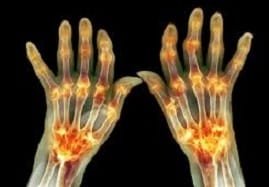

The second form of arthritis is RA. It more commonly affects women than men.

It can deform and debilitate the joints over time. RA causes pain, inflammation, and fluid buildup in the joints as the body’s immune system attacks the membrane that lines the joints.

Turmeric or Haldi is a bright yellow spice that is often used in Ayurvedic remedies. Curcumin in turmeric has anti-inflammatory, antioxidant, and anti-cancer properties that can significantly reduce joint pain. Turmeric is widely used in cooking in a lot of South Asian countries. Its anti-inflammatory properties are significantly helpful for people with rheumatoid arthritis, in which the body’s immune system starts attacking itself, leading to inflammation and pain in the joints.